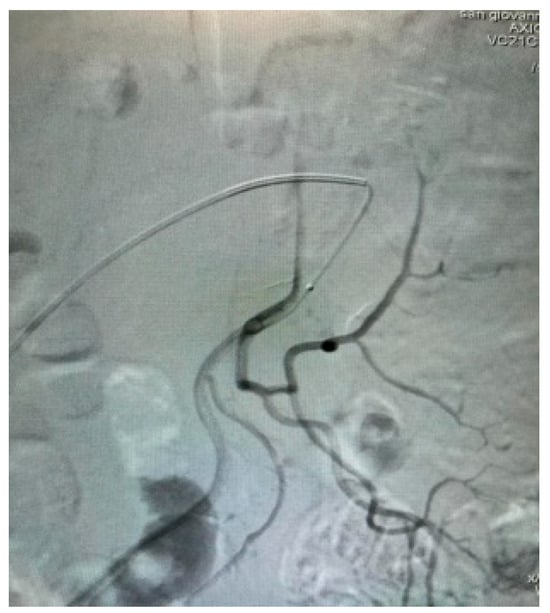

Appendix A.4. Clinical Case 4: Onyx Use in Endoleak Type 1 Excision Post EVAR ABI